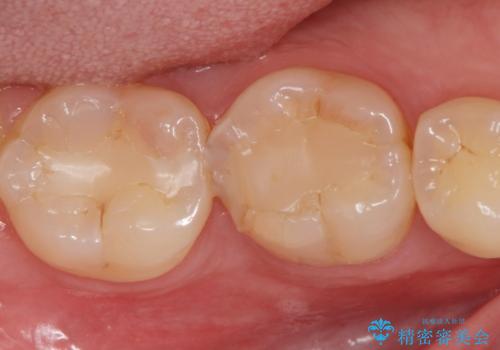

コンタクトカリエスの治療。(e-maxインレー)

拡大鏡下で虫歯を全て取り除き、e-maxインレーで治療を行いました。

適合の良い詰め物が入りました。

歯と歯の間の虫歯は歯ブラシでは予防しずらく、フロスを毎日行わないと虫歯になります。